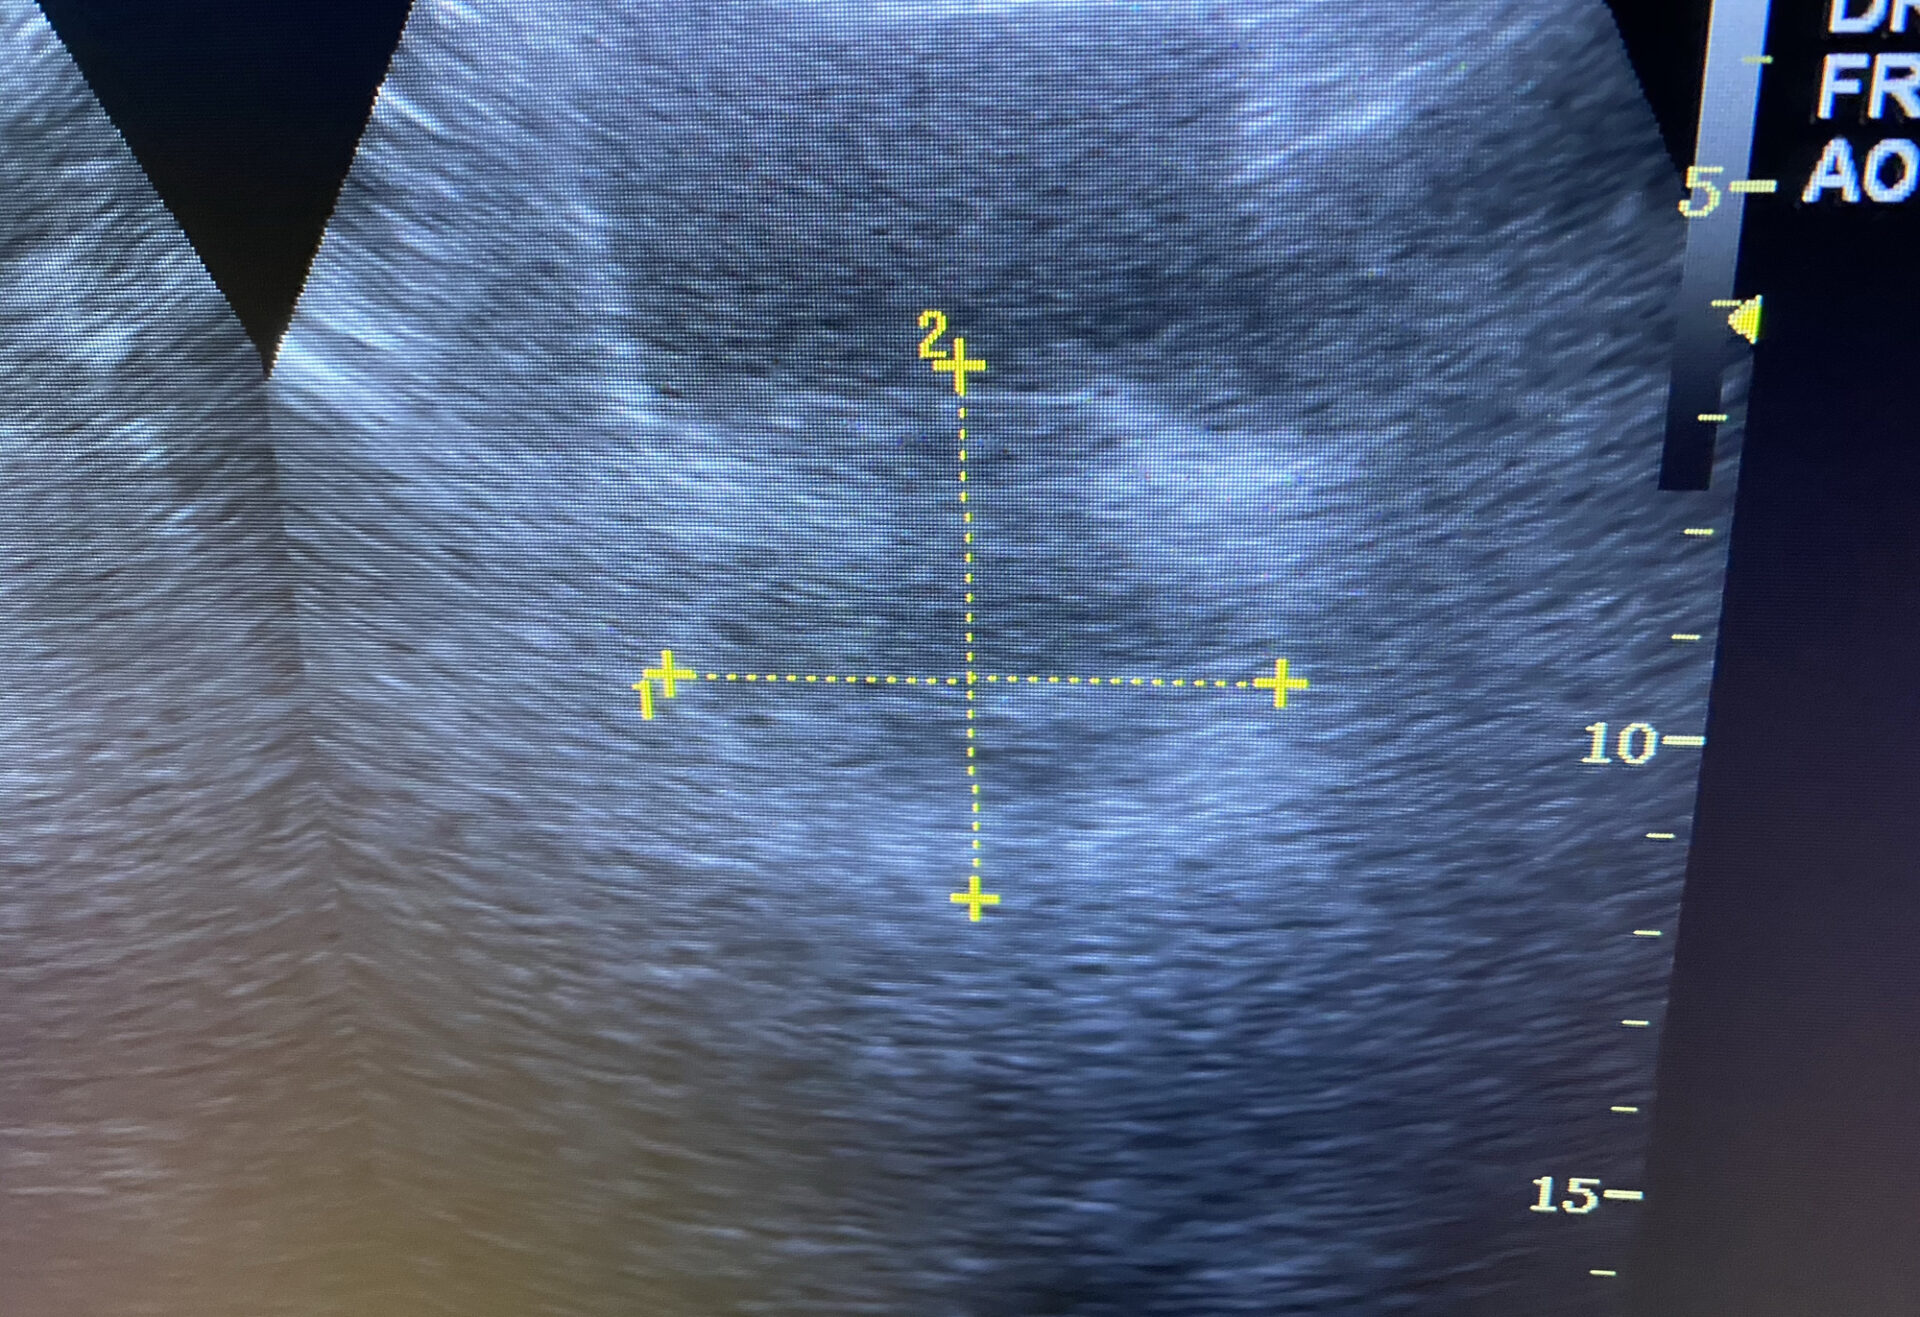

Abdominalschmerz – Prostataabszess

Komplizierte Nierenzysten